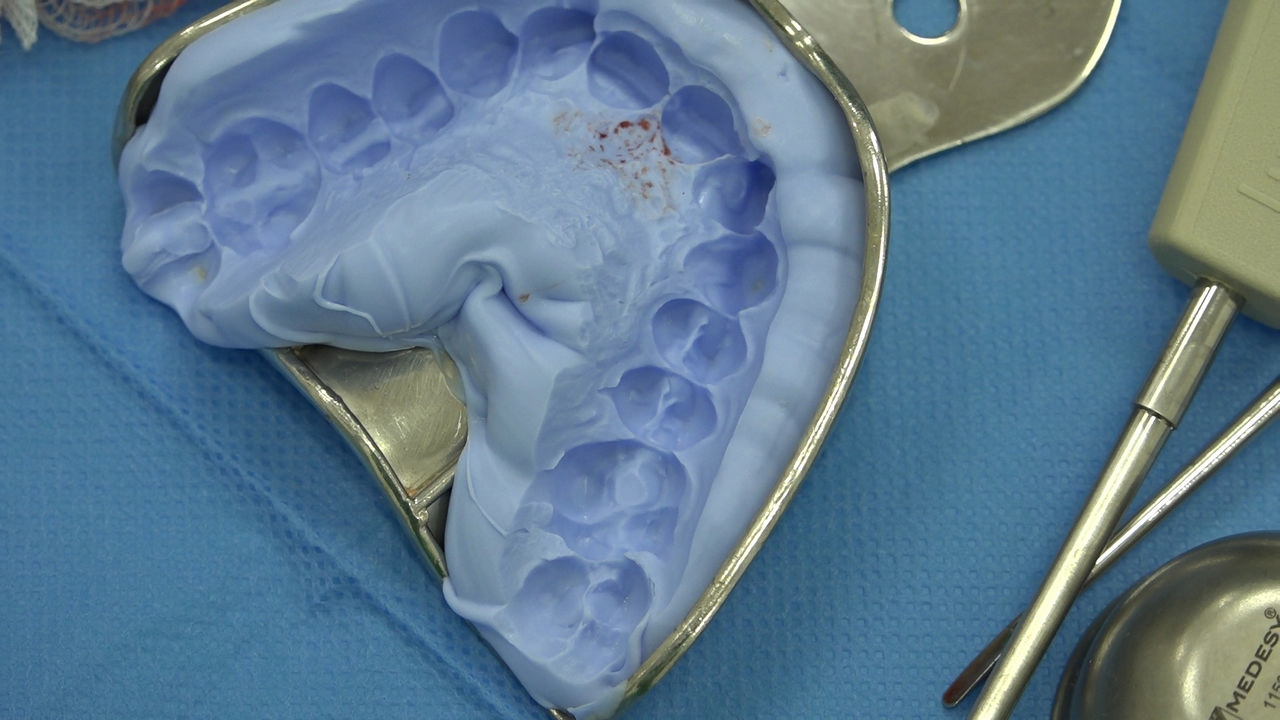

7 Sesja X Sezonu Practiculum Implantologii, w której brali udział kursanci z Grupy A i B, obejmowała implantacje wykonane systemem Axiom, procedury regeneracyjne tkanki kostnej i zabieg sinus lift oraz procedury implantoptotetyczne. Ten zakres szkolenia poprowadziła dr Małgorzata Piotrowska. Protetyka na implantach, to finalny etap leczenia implantologicznego decydujący o uzyskaniu harmonijnego łuku zębowego, okluzji oraz szczelności połączeń, a więc zadowoleniu Pacjenta i powodzeniu całego procesu leczenia.

Jego sednem jest wybór optymalnego rozwiązania rekonstrukcji protetycznej uwzględniający bardzo wiele czynników o charakterze mechanicznym, funkcjonalnym i estetycznym, związanych ze stanem tkanki kostnej, jamy ustnej i uzębienia. Odbywa się już na etapie tomografii komputerowej i jest ściśle powiązany z częścią chirurgiczną, ponieważ prawidłowe zaplanowanie pracy i usytuowania implantów wspomagane plastyką tkanek miękkich, to dla procedur protetycznych baza wyjściowa. Zasady te są jak najbardziej oczywiste, zarówno przy samodzielnym wykonywaniu leczenia implantologicznego, jak i przy podziale zadań dla chirurga i protetyka, czyli pracy w duecie.